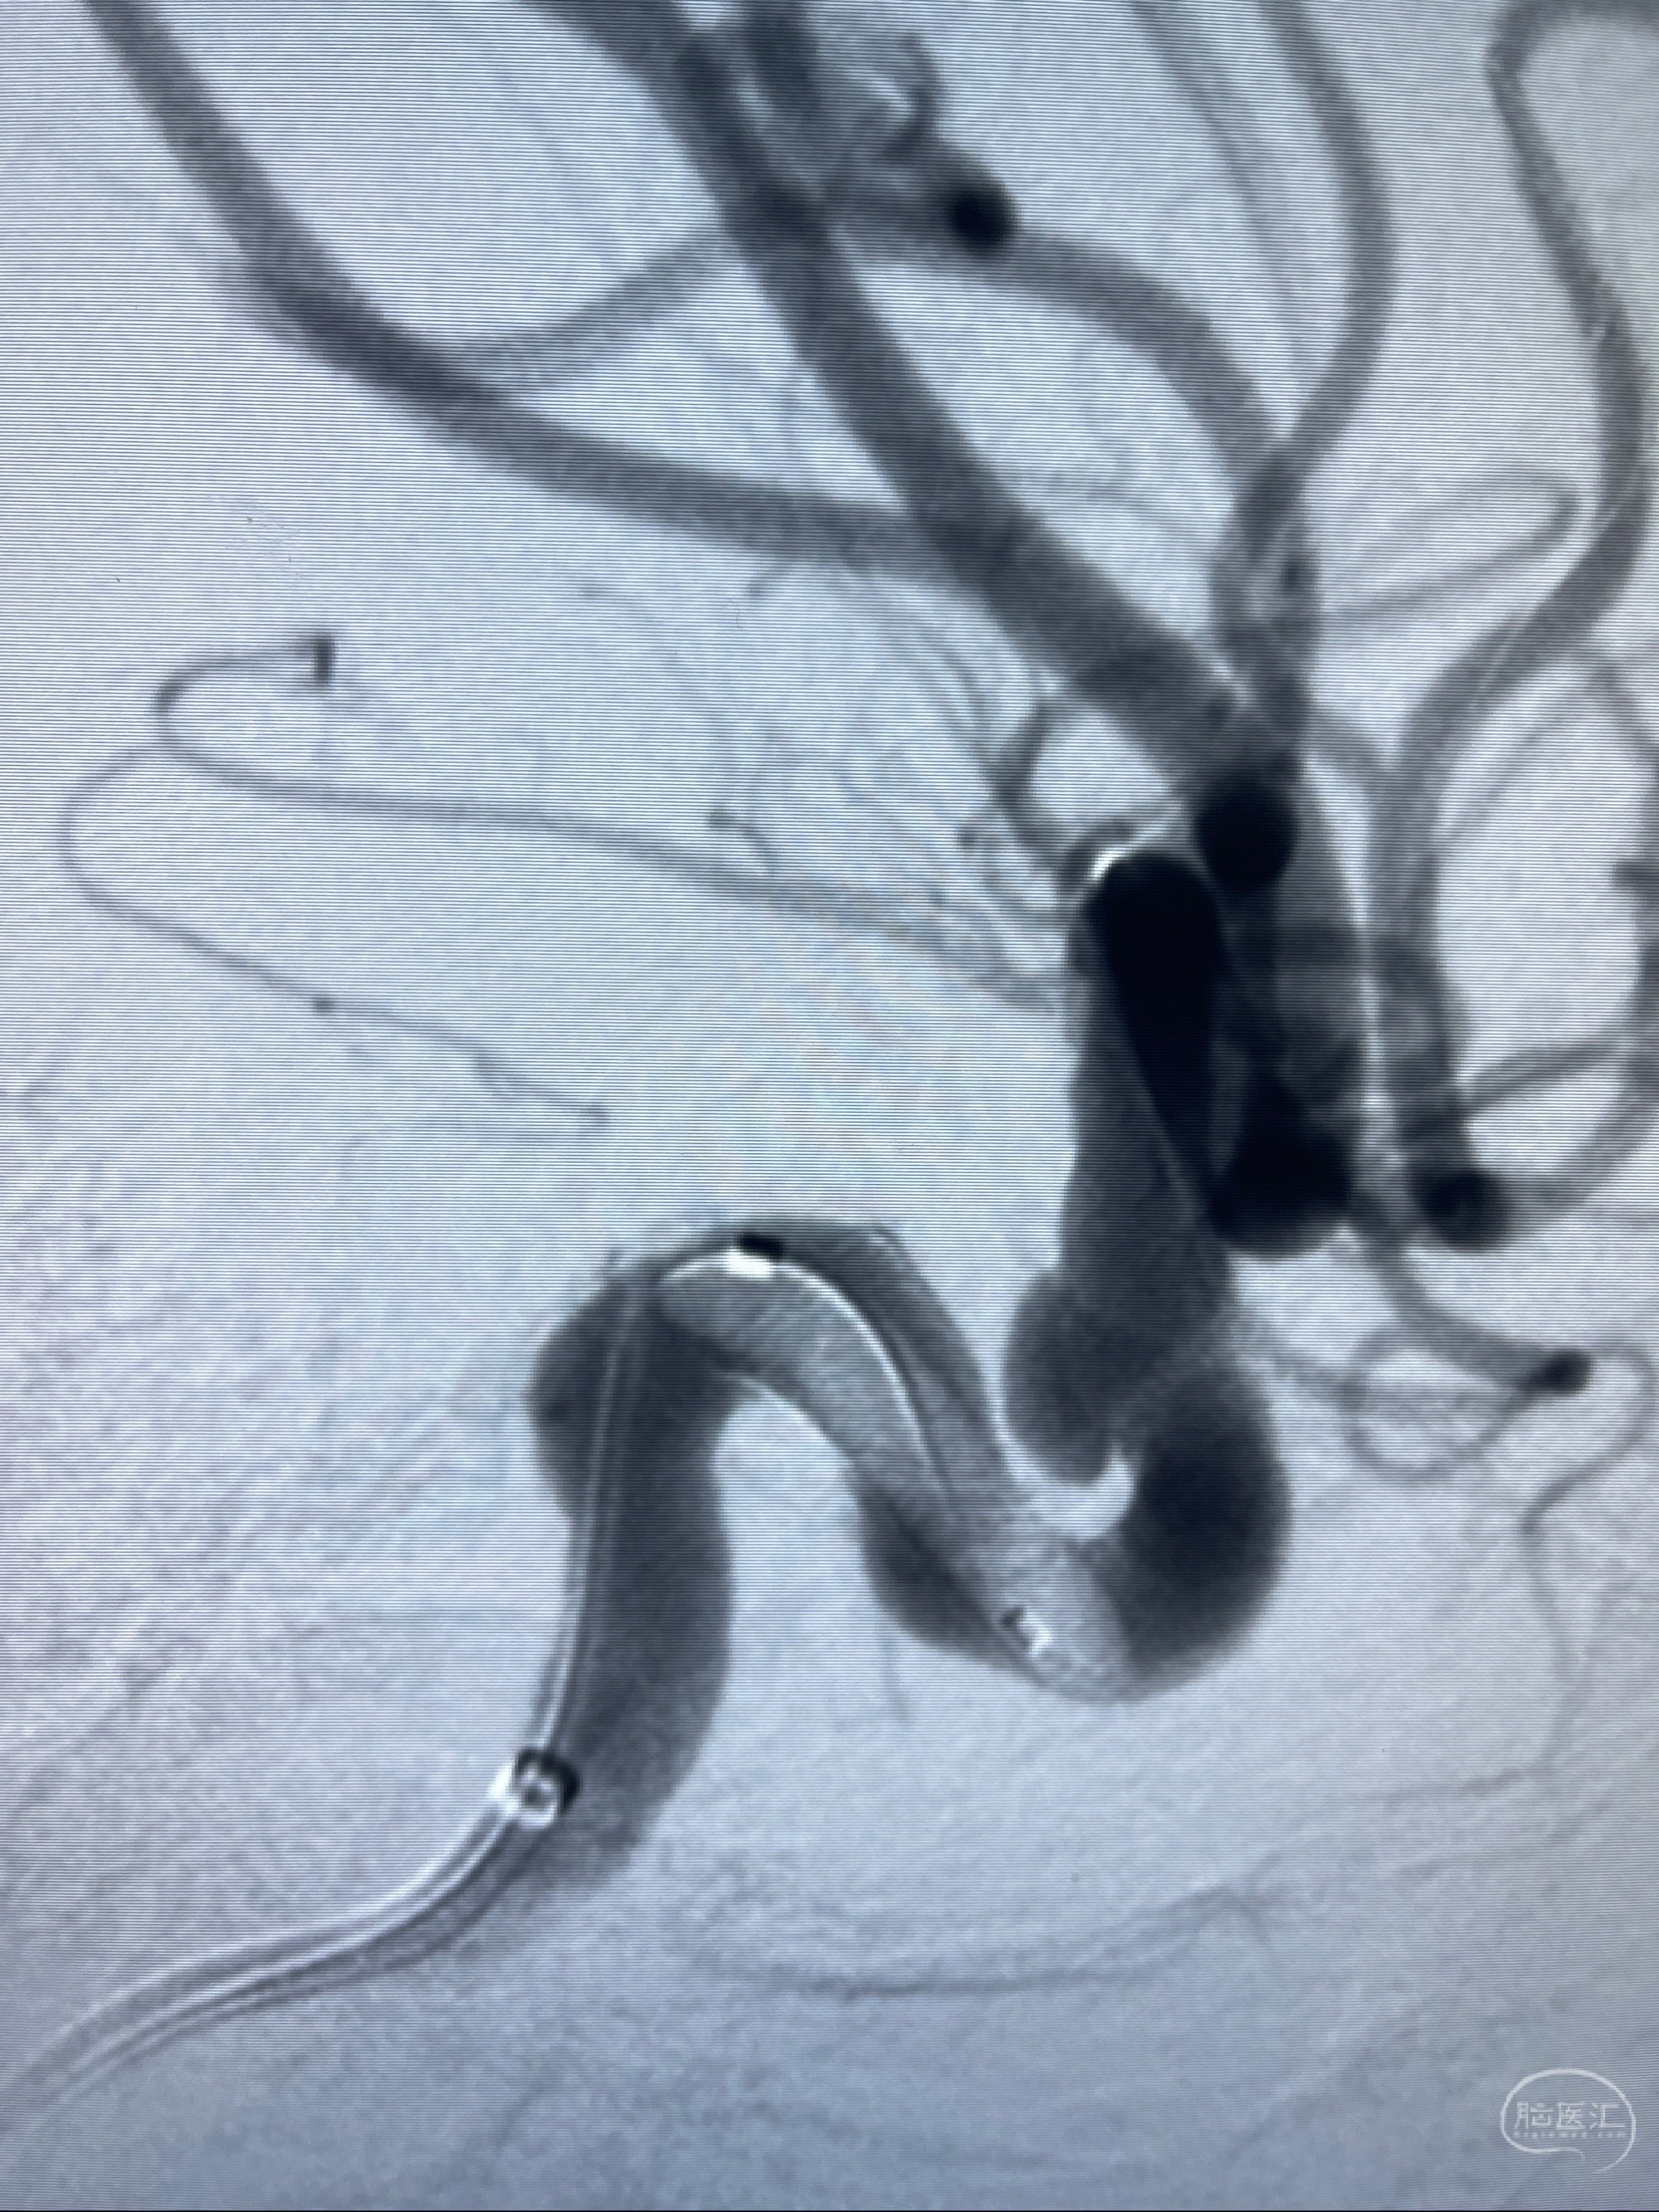

手术顺利,麻醉苏醒佳,遵嘱动作

术后即刻CT